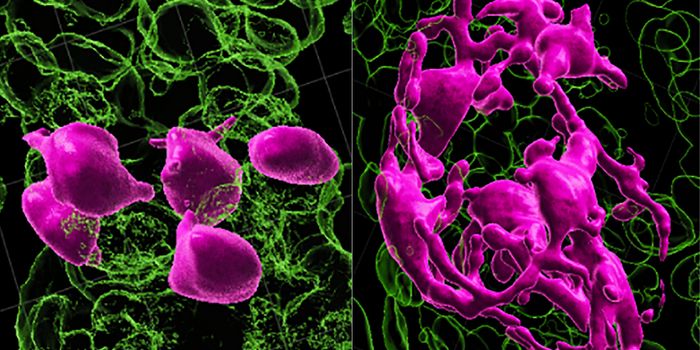

SEP 04, 2023CancerMetastasis is one of the main obstacles in treating cancer. Studying circulating tumor cells (CTCs) and CTC clusters at ...